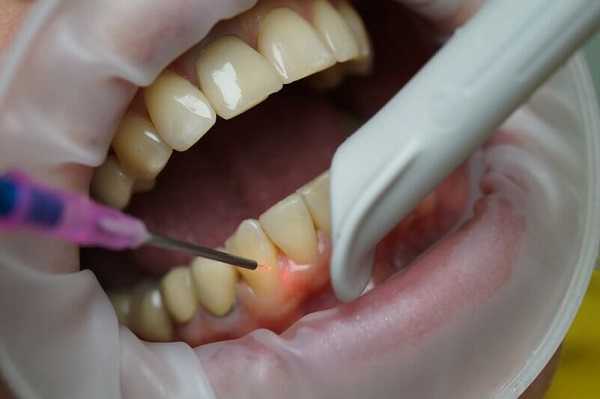

- Диагностическая пункция. Чтобы выяснить, не является ли кистозное образование злокачественным, проводят пункцию толстой иглой. Содержимое ненагноившейся радикулярной кисты представляет собой желтую жидкость со взвесью холестериновых зерен.